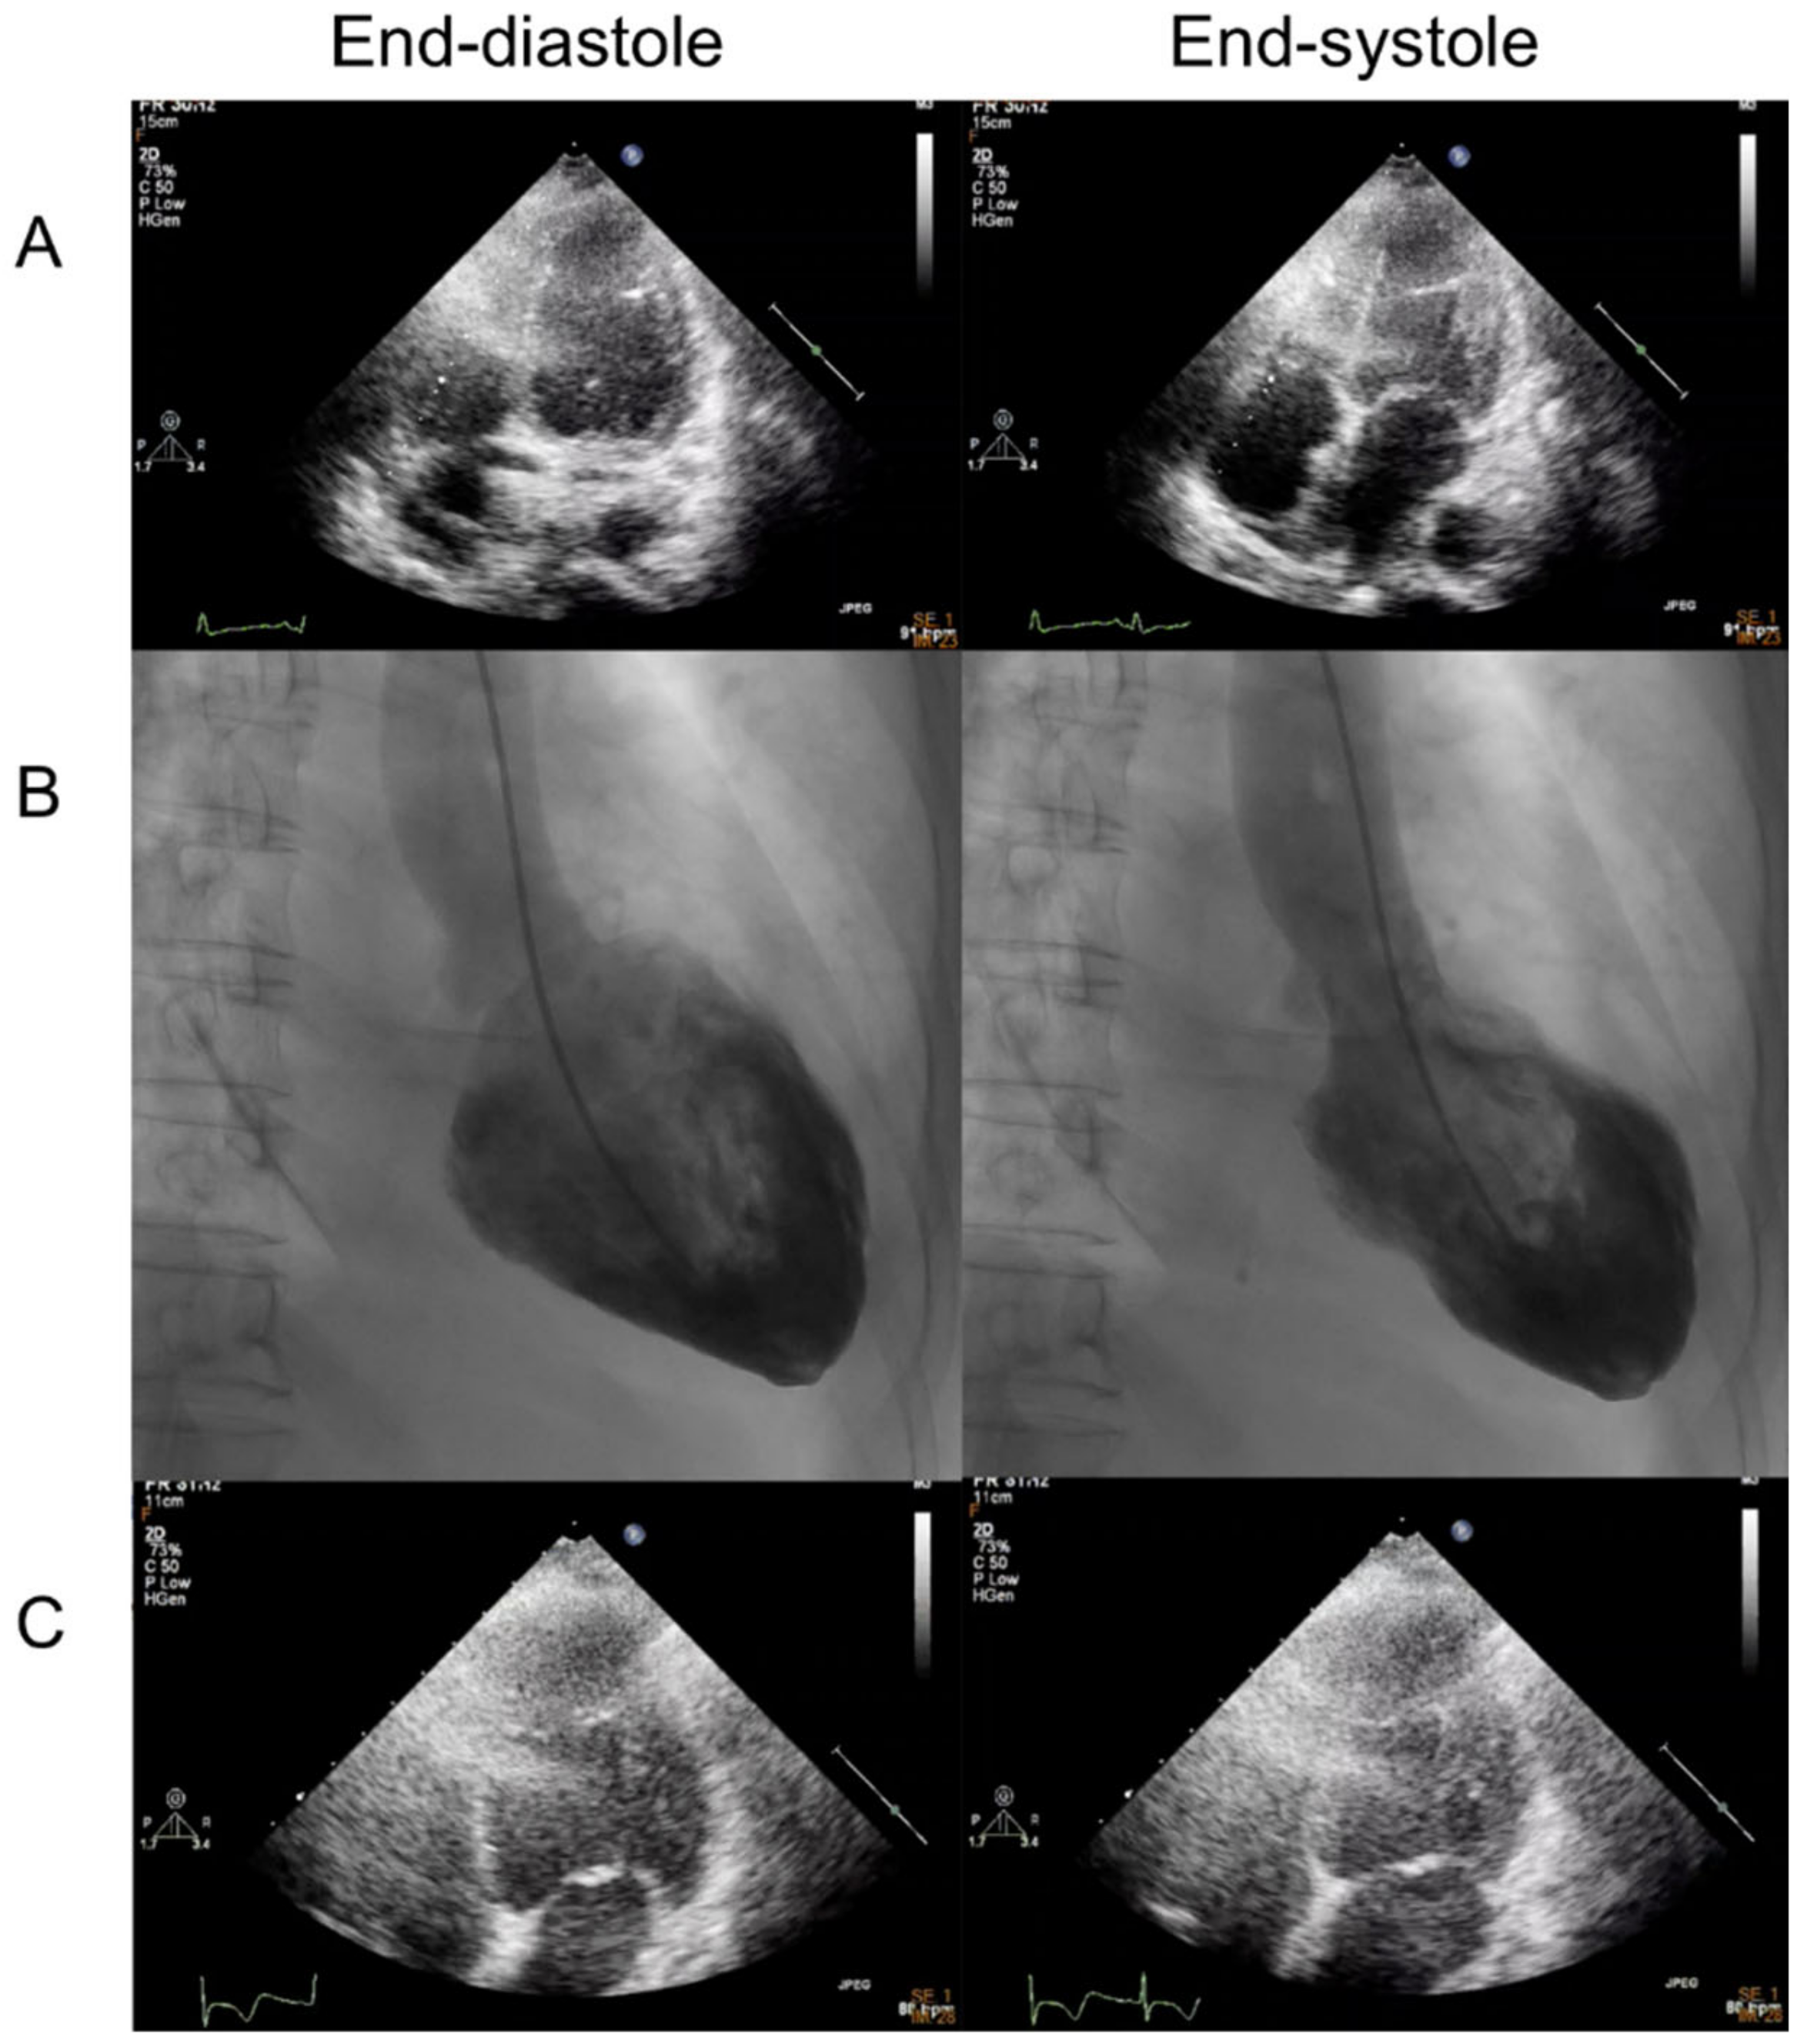

Echocardiography showed reduced left ventricular systolic function as an ejection fraction of 45% and akinesia of apex with preserved systolic wall motion in mid-ventricular and basal left ventricle of the heart (Figure 2A and Supplementary Video S1). Coronary angiography revealed the absence of obstructive coronary artery disease (Figure 3). The left ventriculography showed a typical feature with apical ballooning (Figure 2B and Supplementary Video S2).

Figure 3. Coronary angiography showed no remarkable atherosclerotic change or stenosis of coronary arteries. (A) RAO cranial view. (B) LAO cranial view.